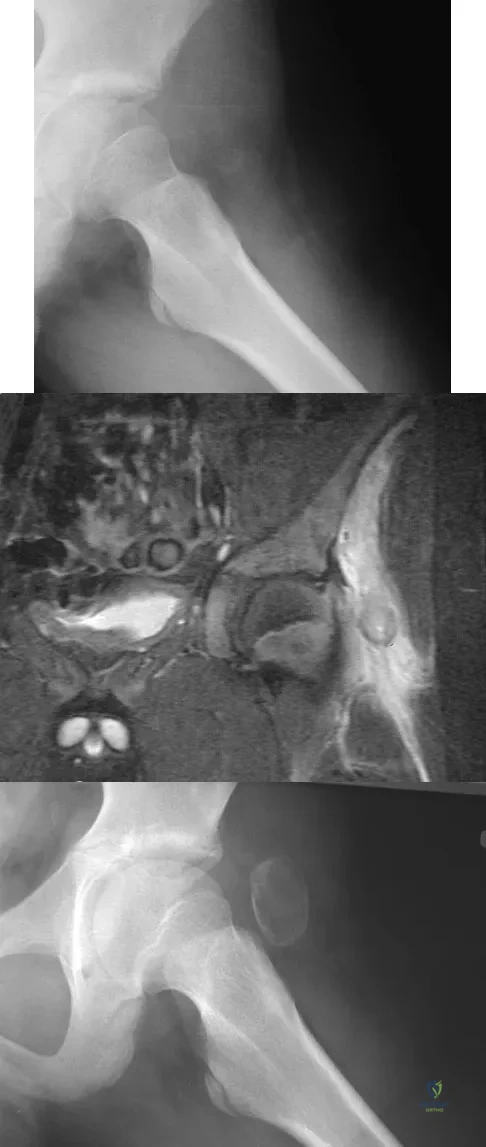

A 13-year-old boy has a painless "knot" over his left hip. History reveals that he injured his left hip playing soccer 4 months ago. A radiograph and MRI scan obtained at the time of injury are shown in Figures 7a and 7b. He is very active and is currently asymptomatic. A current radiograph is shown in Figure 7c. What is the next most appropriate step in management?

Explanation

Question 16

A 16-year-old girl injured her hip in a fall. Radiographs are shown in Figures 14a and 14b. She denies any history of pain prior to the fall and is currently asymptomatic. A bone scan, MRI scan, and biopsy specimens are shown in Figures 14c through 14f. What is the most likely diagnosis?